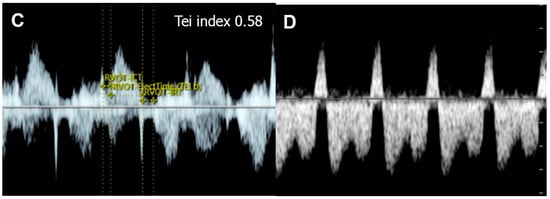

| Tei index | Increased > 0.50 | Global cardiac dysfunction |

| ICT: 28 (22–33) ms | Prolonged | Systolic dysfunction |

| IRT: 34 (26-41) ms | Prolonged | Diastolic dysfunction |

- Mori, Y.; Rice, M.J.; McDonald, R.W.; Reller, M.D.; Wanitkun, S.; Harada, K.; Sahn, D.J. Evaluation of systolic and diastolic ventricular performance of the right ventricle in fetuses with ductal constriction using the Doppler Tei index. Am. J. Cardiol. 2001, 88, 1173–1178. [Google Scholar] [CrossRef]